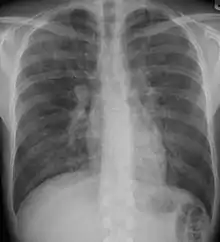

![]() | |

| End-stage pulmonary fibrosis of unknown origin, taken from an autopsy | |

X-rays

Chest radiography is usually the first test to detect interstitial lung diseases, but the chest radiograph can be normal in up to 10% of patients, especially early on the disease process.[10][11]

High resolution CT of the chest is the preferred modality, and differs from routine CT of the chest. Conventional (regular) CT chest examines 7–10 mm slices obtained at 10 mm intervals; high resolution CT examines 1–1.5 mm slices at 10 mm intervals using a high spatial frequency reconstruction algorithm. The HRCT therefore provides approximately 10 times more resolution than the conventional CT chest, allowing the HRCT to elicit details that cannot otherwise be visualized.[10][12]

Radiologic appearance alone however is not adequate and should be interpreted in the clinical context, keeping in mind the temporal profile of the disease process.[10]